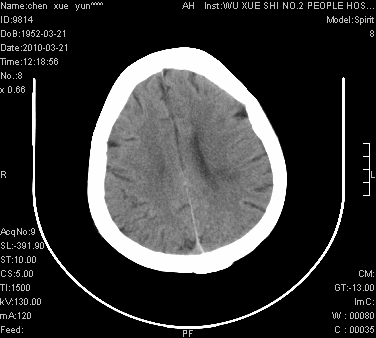

性别:不详;年龄:58岁;病史:不详。

ct表现:1、右侧额颞叶深部不规则钙化密度团块,呈弯曲条带状,占位效应不明显,考虑少枝胶质细胞瘤可能性大于血管瘤。2、右枕叶大片不规则低密度影,密度近似于脑脊液,右侧侧脑室后角及三角区扩张,考虑为陈旧性脑梗塞。

讨论:1、这个病灶的钙化有点像脑回样钙化,因此我最初考虑颅面血管瘤病(sturge-weber综合征),但是查阅了我们网站上的几个颅面血管瘤病病例,钙化均位于脑实质表面,沿脑回分布,而这例病灶位置较深,因此可以否定“颅面血管瘤病”这个诊断。

2、卜一会员曾经说过:少枝胶质细胞瘤的典型征象为弯曲条带状钙化,可作为定性的可靠征象(http://www.radida.com/news_view.asp?id=5150)

3、血管瘤也可以出现弯曲条带状钙化,但血管瘤多数出现“负占位”效应,即病灶周围的脑室、脑池及脑沟不是受压变窄,而是局限性的增宽。